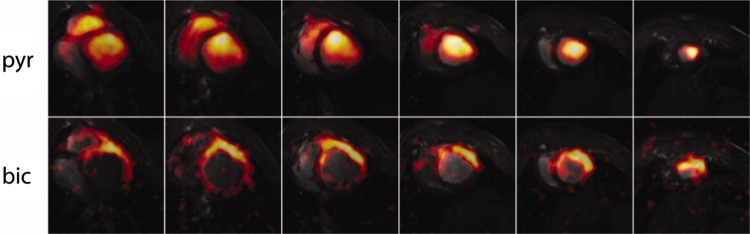

Fig. 13.

In vivo short-axis pig heart multi-slice dynamic cardiac-gated images of hyperpolarized 13C pyruvate (top row) and bicarbonate (bottom row) acquired with a spiral k-space trajectory after single-metabolite-resonance spectral-spatial RF excitations.

Reproduced with permission from Lau et al. [70]